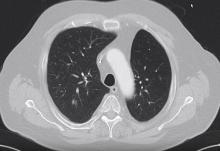

This video demonstrates the case of a 73-year-old patient with a history of colon carcinoma, prostate carcinoma, and contralateral lobectomy for non-small cell lung cancer. The patient was admitted for a 12 mm large nodule in the posterior segment of the right upper lobe. Distant metastasis was excluded and a video-assisted thoracoscopic (VATS) segmentectomy and lymphadenectomy was planned.